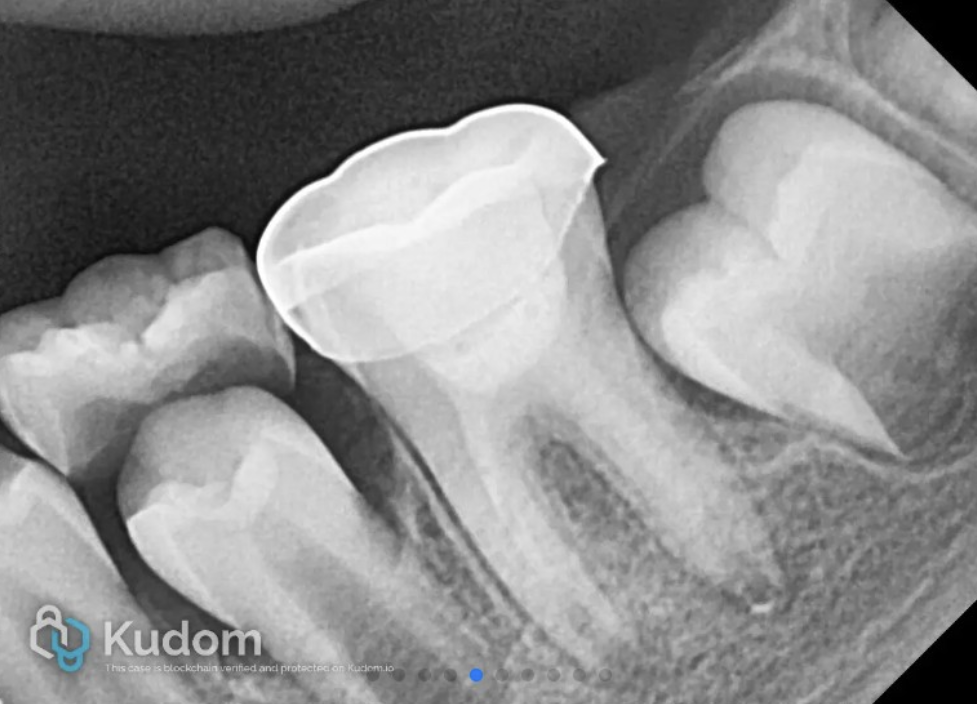

The X-ray shows the placement of calcium hydroxide medicament in the canals.

Fig. 3

The length at which tactile feedback was received was considered to be the working length. The canals were then irrigated with 20 mL of 1% sodium hypochlorite for 5 minutes. A side-vented needle was used to deliver the irrigant, with the tip placed 2 mm short of the determined working length.

Following irrigation with sodium hypochlorite, the canal was thoroughly flushed with 5 mL of sterile physiological saline to neutralize residual irrigant in the canals and protect periapical tissues. The canals were then dried using sterile paper points.

A final irrigation was done with 20 mL of 17% EDTA to reverse the toxic effects of sodium hypochlorite, and to recover the cell viability. The pulp chamber and canals were dried with sterile paper points and calcium hydroxide medicament (Ultracal XS; Ultradent Products Inc., South Jordan, Utah) was placed loosely into the canal orifices without pressure, cavity closed with glass ionomer cement and patient was recalled after 3 weeks.